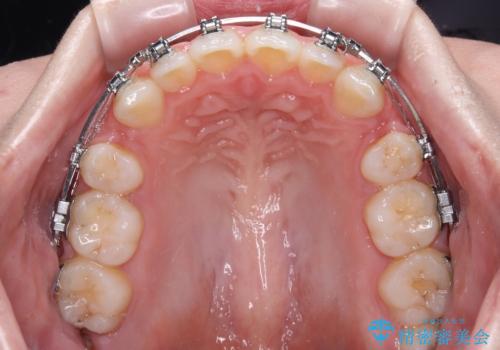

- メタルブラケット

舌の突出癖により上下前歯は接触できず、更には前方に押し出されて出っ歯になっている状態でした。

上下左右の第一小臼歯4本を抜歯し、ワイヤー装置での抜歯矯正を行っていくのですが、原因である舌の突出癖を改善しないことには治療がうまく進められないため、舌のトレーニングを徹底するよう指導していくこととしました。

当初は舌のトレーニングをしっかりと行ってくださったおかげで、短い期間で治療を終えることができました。